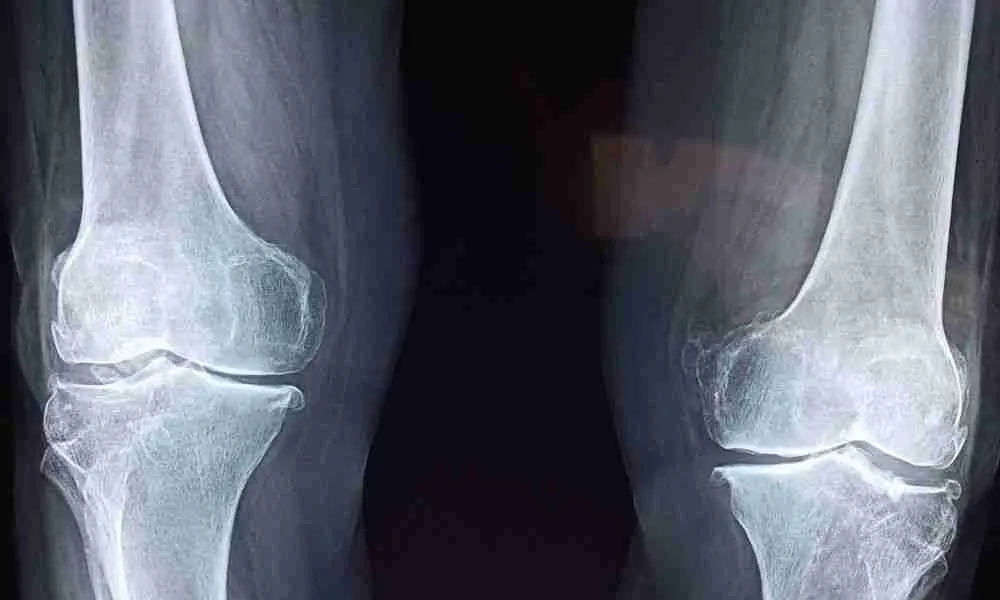

Knee arthritis, a degenerative joint condition, affects millions worldwide, reducing mobility and quality of life. As patients explore alternatives to traditional treatments, Platelet-Rich Plasma (PRP) therapy has gained traction as a promising intervention. This blog delves into the nuances of PRP for knee arthritis, including its success rates, what patients should know, and what they can expect from this innovative treatment.

Success Rates For Knee Arthritis

Studies and clinical trials have shown varying success rates for PRP in treating knee arthritis. While individual results differ, many patients report significant improvements in pain and mobility.